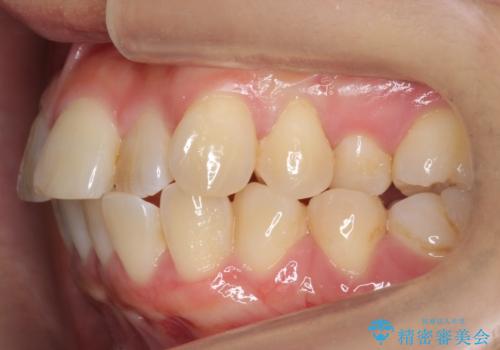

[ 前歯のねじれ・がたつき ] マウスピース矯正

![[ 前歯のねじれ・がたつき ] マウスピース矯正の症例 治療前](https://seimitsushinbi.jp/wp/wp-content/uploads/2024/02/4007c6479f6bce11863dcdd32ed5e39b-500x350.jpg?v=1708502552)

![[ 前歯のねじれ・がたつき ] マウスピース矯正の症例 治療後](https://seimitsushinbi.jp/wp/wp-content/uploads/2024/02/e7a01485e4f4dd0da04705fde4cc34cc-500x350.jpg?v=1708502585)